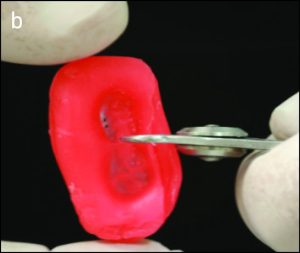

The contact areas of the teeth must not be disrupted during the procedure; otherwise, tooth migration or food impaction may occur. Using the same bur, the buccal and lingual extensions of the rest seat are prepared. In general, creating adequate space on the buccal side is more difficult than on the lingual side. Clearance can be checked by placing two clasp wires side by side. These clasp wires are positioned in the embrasure area, and if the patient can comfortably bring the teeth into occlusion, sufficient space is confirmed. The shape and depth of the rest seat can also be evaluated using pink wax. A disc-shaped piece of pink wax is placed on the prepared tooth and molded by bringing the teeth into occlusion. After examining the wax surface to verify the shape of the rest seat, the thickness of the wax in the seat area area is measured with calipers (Figure 10-41), thus determining the depth of the preparation.

|

a) Adequate preparation must be performed on both the buccal and lingual surfaces.

b) The depth can be evaluated using a disc-shaped piece of pink wax, which is shaped by bringing the teeth into occlusion.